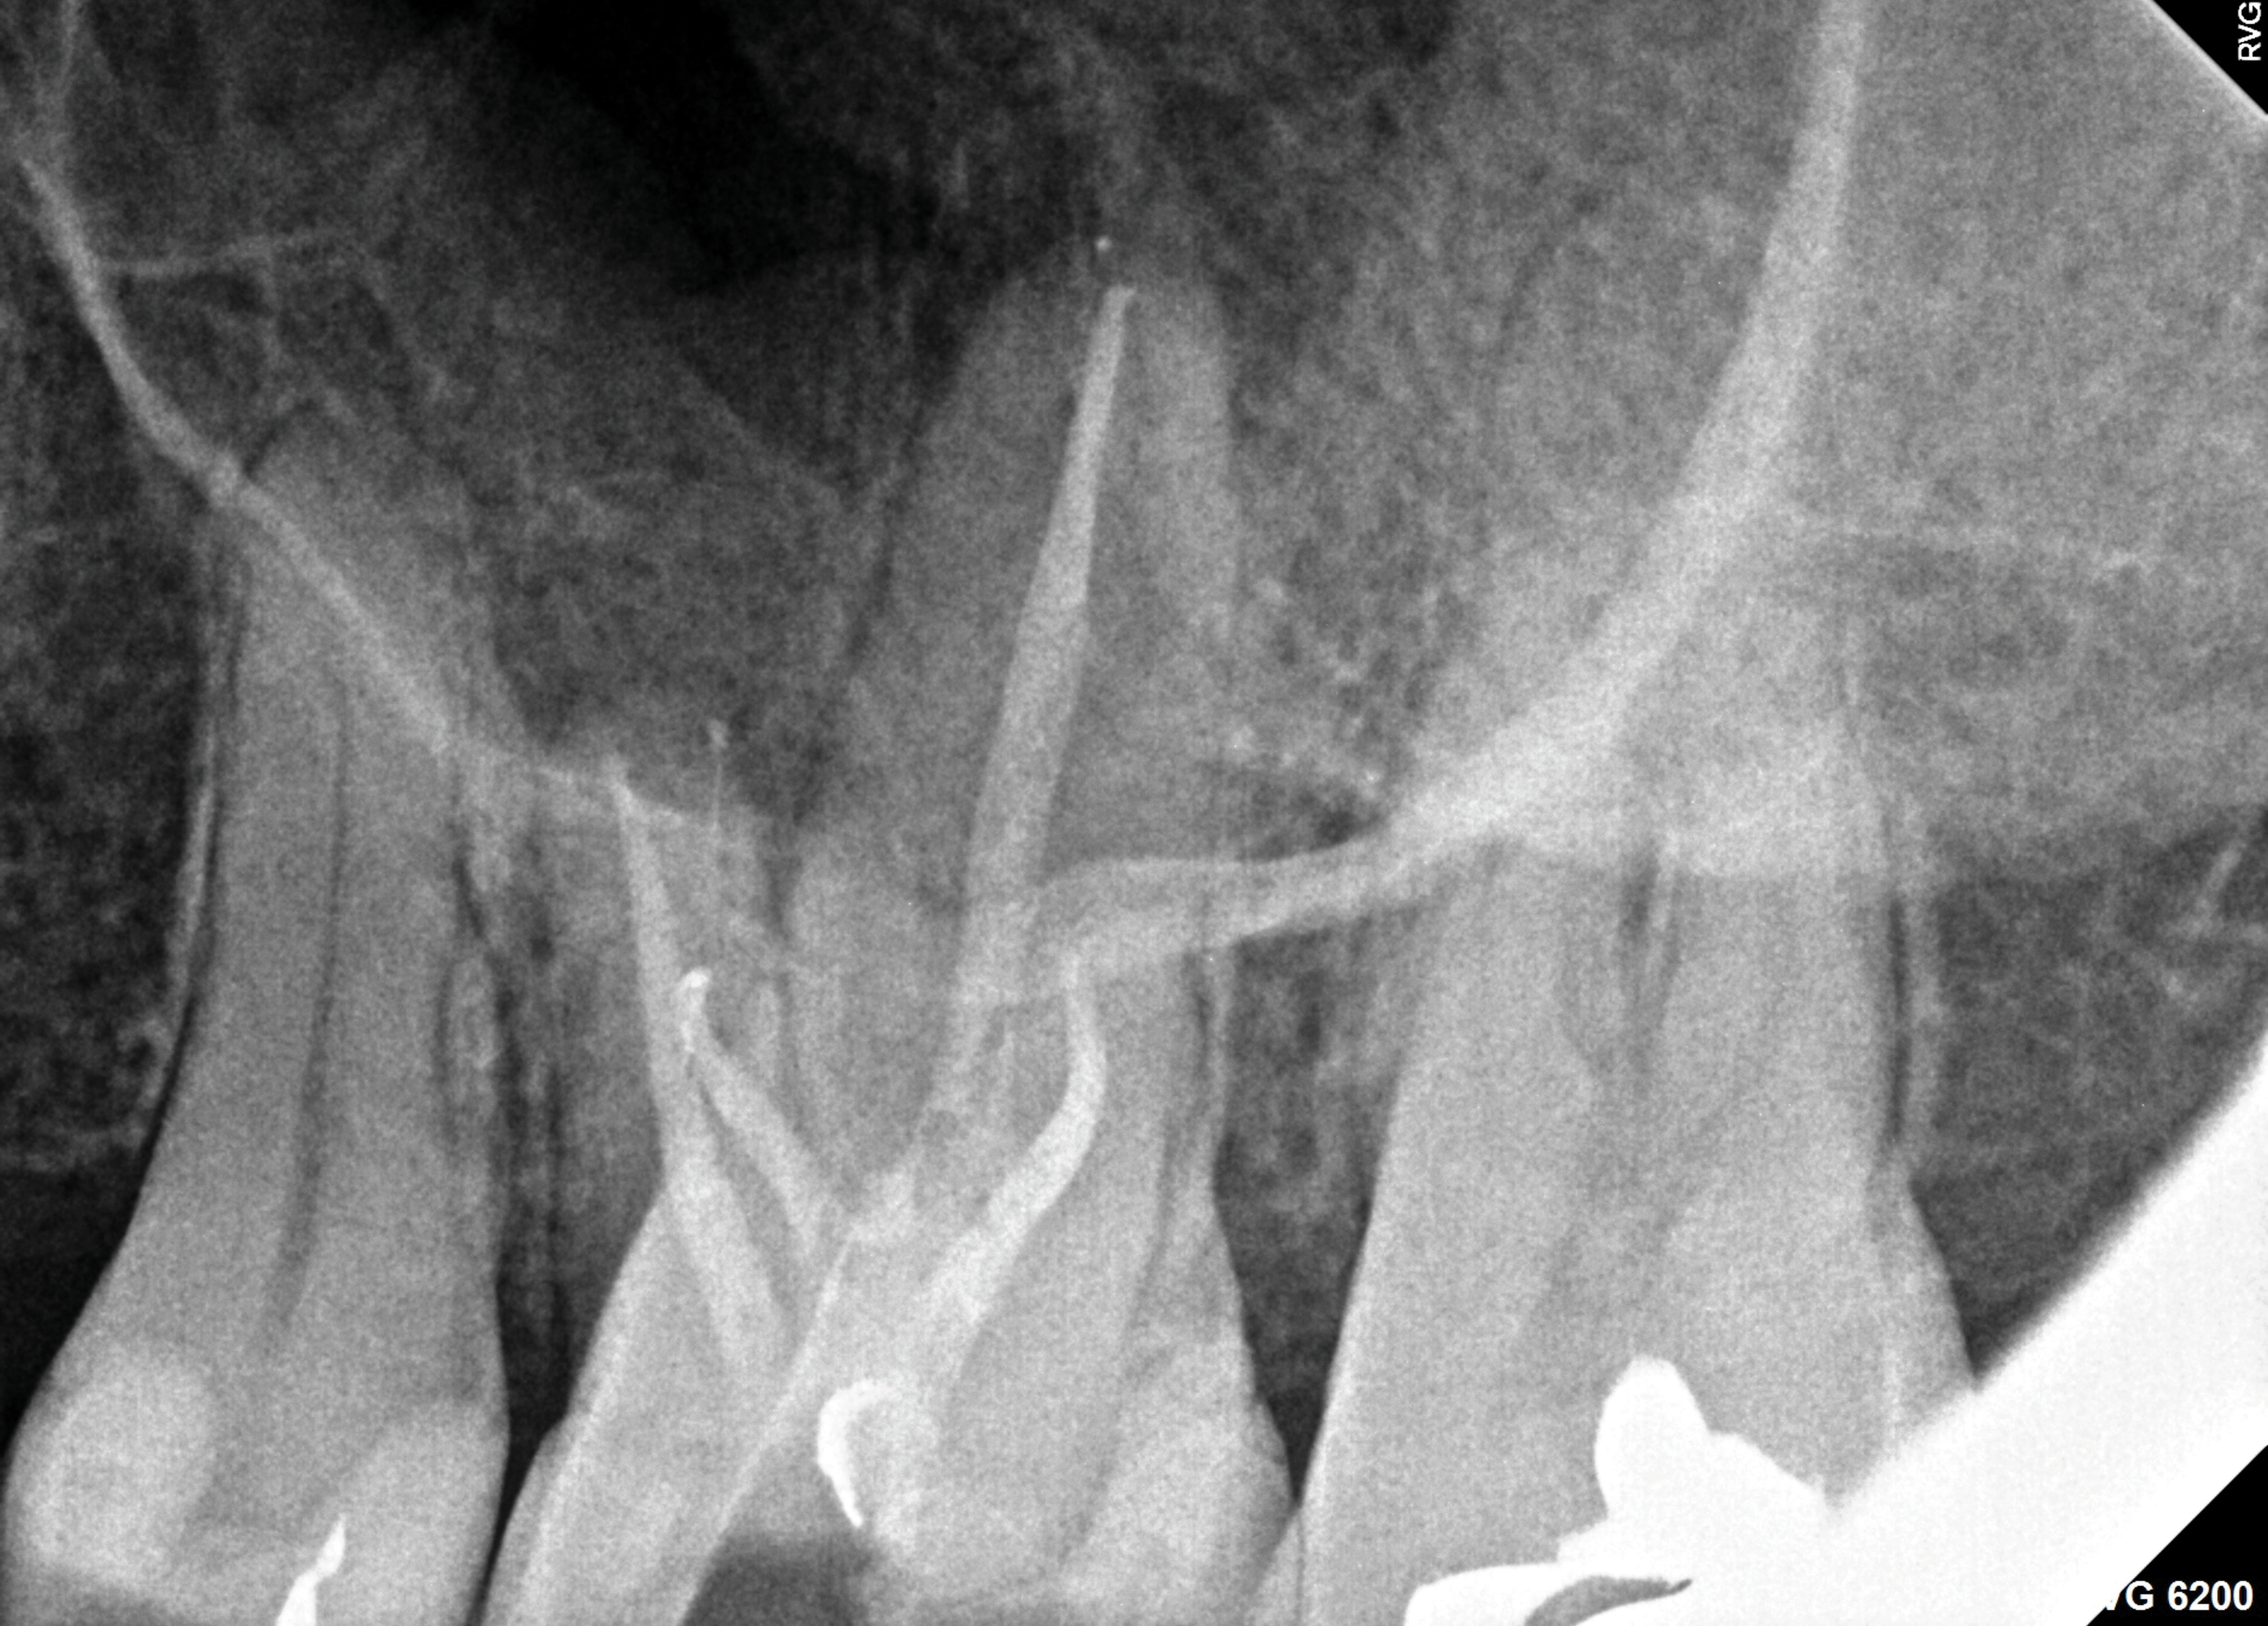

A 52-year-old male patient was seen by his otolaryngologist for symptomatic and unilateral sinusitis of 6 months duration. Medical CT showed dental pathology (Figure 5). His general dentist had a bitewing radiograph on file and referred the patient for endodontic evaluation (Figure 6).

Fig 6. Preoperative bitewing imaging from general dentist.

Figure 6